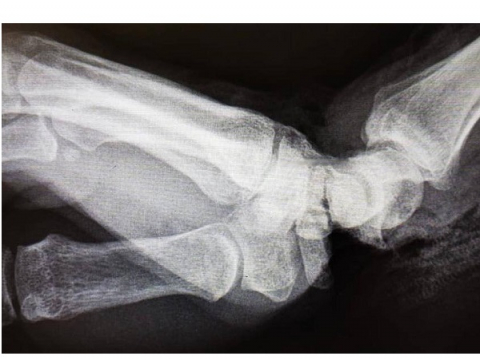

Согласно информации, пострадавшая повредила руку на производстве во Владимире. Женщина получила удар ножом для резки плёнки в область сочленения и предплечья. Когда её привезли в БСМП Владимира, кисть руки была почти оторвана и держалась лишь на небольшом лоскуте кожи.

После остановки кровотечения пациентку в экстренном порядке транспортировали в клинику ПИМУ. В отделении травматологии и ортопедии пострадавшую прооперировали. Кисть руки удалось спасти.

Фото: Университетская клиника ПИМУ в соцсети «ВКонтакте»